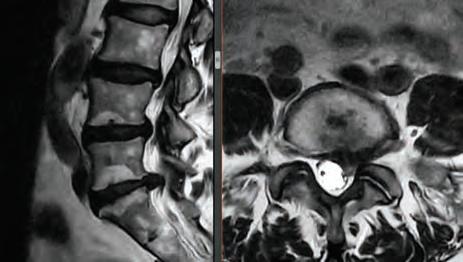

Avoiding and Manipulating a Dowager’s Hump

Dowager’s hump, neck hump, text hump, hunchback, or round back area all names for the same condition. There are a few different labels for the excessive bend in your spine. There are a number of difference causes of dowager’s humps, the most prevalent of which are postural, congenital, and Scheuermann’s.

What is a dowager’s hump?

Considered a spinal condition, the chronic forward-leaning posture that is all too frequent in our world of computer screens and other devices is the cause of this ailment, is named “kyphosis” in the medical community. If you have a propensity of slouching all the time, it’s possible that your top vertebrae will develop an unnatural bend over time. Your spine has natural curves to it, which helps you stand straight and supports your posture, but kyphosis can affect your posture and make standing a challenge.

What causes it?

Poor posture is the leading contributor to the development of a dowager’s hump. Because of this, a dowager’s hump most commonly appears between the ages of 40 and 60. Ths forward-leaning and humped posture is frequently the result of tight muscles in the chest and neck, as well as weak muscles in the upper back and neck. Other possible causes include:

• Osteoporosis. A compression fracture causes an increased forward curve. Ths causes your upper back to curve more, which forces you to lift our neck into more extension to be able to see forward. It’s those two factors that cause the bump in the upper back. Women are more likely to develop a Dowager’s hump, as hormone changes during menopause can increase their risk of osteoporosis.Degenerative changes in your spine. Ths is a slow, progressive loss of the normal structure and function of your spine. Degenerative changes range from mild to severe and most often occur as a result of the normal aging process. Arthritis, tumors and infections can also cause these changes.

Hyperkyphosis is when the curve of your spine is extreme, is associated with impaired lung function, reduced functional capacity and increased higher risk for death.

Symptoms of dowager’s hump might vary from person to person, but depending on the degree to which nerves are involved, radicular pain, tingling, and/or numbness that can be felt throughout the body. The severity of symptoms, such as troubles with the bowel or bladder, problems with balance and coordination, and impaired lung function, can increase if the condition is either allowed to go untreated or is not addressed aggressively.

If you suspect you may have a dowager’s hump, the fist step of treating a neck hump is to determine the cause. Talk to your primary care physician to rule out any underlying issues.